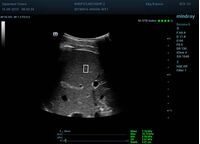

Определение плотности печени. Не ошибся ли оператор при измерении эластических свойств печени? Для оценки критериев качества предусмотрен индекс MBT, который покажет насколько «твердой» была рука оператора и двигалась ли печень. При MBT 5* рука тверда и показатели достоверны. Для оценки качества результатов используется IQR индекс, отображающий колебания показателей в точке измерения при расчете медианы. Показатели при IQR <30% считаются приемлемыми. Техника сканирования через межреберные промежутки требует размещение окна интереса на несколько сантиметром ниже капсулы, для исключения эффекта реверберации. Установка ROI на паренхиму без захвата сосудов, для исключения погрешностей измерения.